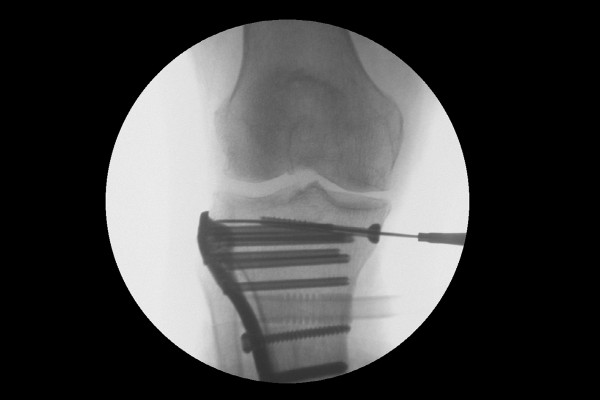

위치를 잘 잡은 후 바깥쪽에서 금속판(Plate)으로 강하게 골절부위를 고정해줍니다.

2f992d7239a97edca630fa072198310c_1766717672_7308.jpg

내측 고평부에도 골절이 있었기 때문에 추가적으로 안쪽에서도 스크류(Screw) 고정을 해줍니다.

2f992d7239a97edca630fa072198310c_1766717682_8849.jpg

수술은 잘 마무리 되었고, 수술 후 X-RAY를 보면 골절되었던 무릎 경골 고평부가 강하게 잘 고정되었음이 확인됩니다.